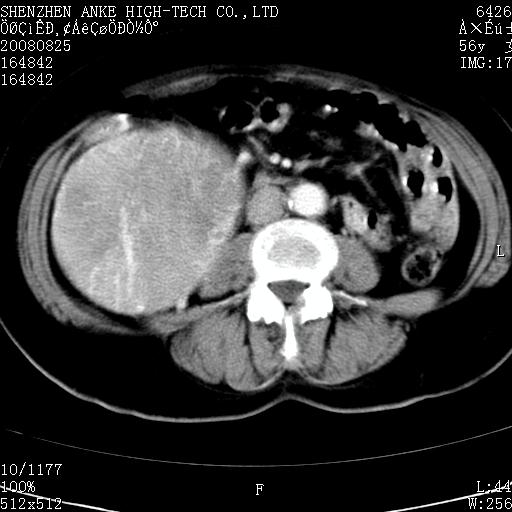

患者,女性,56岁,腰痛3年,查:右腹部约8x10cm肿块,固定,无压痛;8月23日在外院做了平扫,发现右肾巨大肿块(外院具体诊断不祥);今天在我院做了静脉肾盂造影,示:右肾明显增大,分泌功能明显减弱。

1)考虑右肾癌并右肾静脉瘤栓形成。2)脂肪肝。